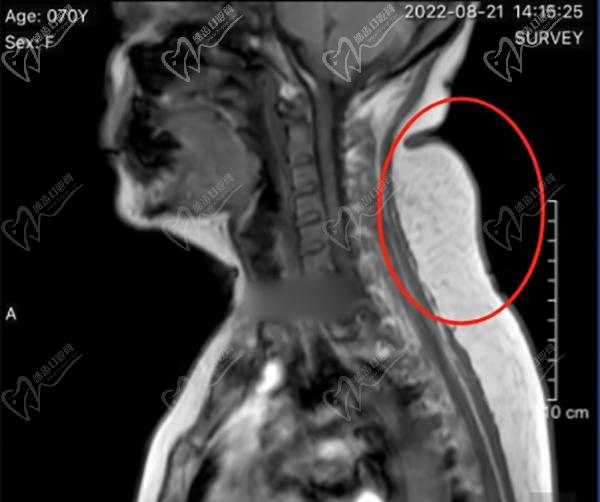

很多嘗試過針灸、按摩、拔罐、艾灸的朋友,當(dāng)時(shí)有點(diǎn)成效,但是沒多久就感覺富貴包變得更大了。韋元強(qiáng)醫(yī)生做的乳化抽吸術(shù)消除富貴包手術(shù),是微創(chuàng)局麻手術(shù),通過乳化的方式將發(fā)硬的脂肪乳化后,再吸出體內(nèi),比較徹 底,術(shù)后很難反彈。整個(gè)手術(shù)過程需要2.5個(gè)小時(shí)左右,手術(shù)僅有1個(gè)針眼大的創(chuàng)口,就在富貴包下面5cm的地方,比較隱蔽,剛做完手術(shù)后會(huì)感覺肩頸放松了很多,后頸部的鼓包也消失了,術(shù)后觀察一段時(shí)間沒有問題就可以出院了。術(shù)后修復(fù)期穿塑身衣加壓消腫就好了。